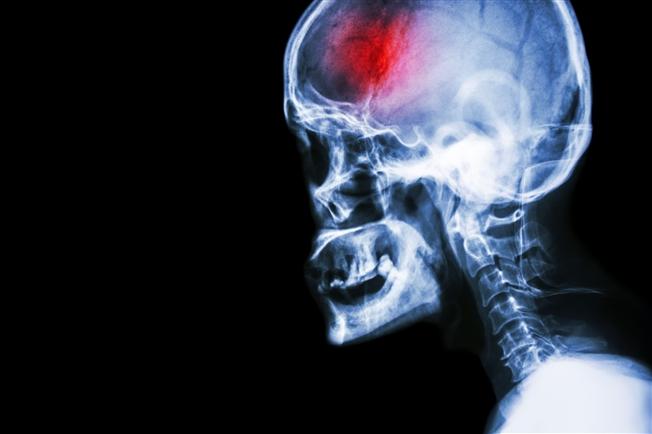

By now, you've probably been warned about the symptoms of a concussion. How long after a head injury can symptoms occur? In many instances, these symptoms don't occur until a few hours after an injury?

After a traumatic accident, a sports injury or a fall, the symptoms of a concussion can be immediate or latent.

The symptoms one develops can vary from person to person, and may include headaches, nausea, dizziness, difficulty remembering, fogginess, irritability, difficulty sleeping or trouble balancing. Symptoms can vary so greatly that it's difficult to pinpoint what exactly you might experience and when.